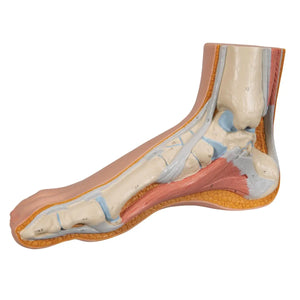

Squelette d'un pied normal

En plus des structures superficielles, les os, les muscles et les ligaments sont représentés et numérotés sur la face interne.

Squelette d'un pied normal

En plus des structures superficielles, les os, les muscles et les ligaments sont représentés et numérotés sur la face interne.